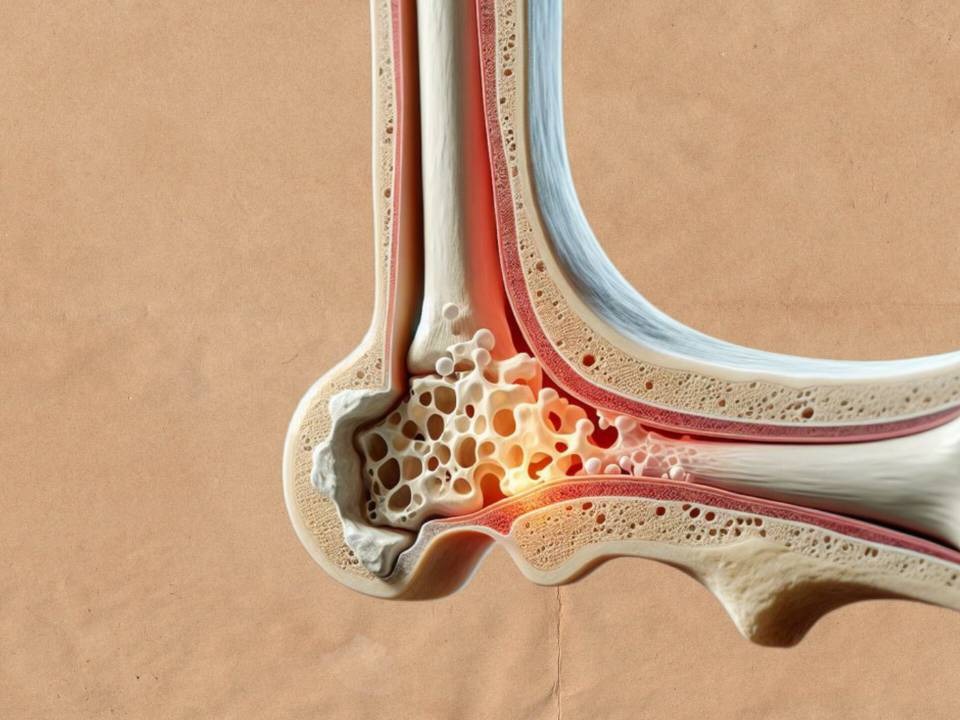

آرتروز

آرتروز یا استئوآرتریت بیماری شایعی که در همه جا دیده می شود. به این بیماری ساییدگی مفصلی هم گفته می شود. یک بیماری تخریبی پیشرونده است ولی التهابی نیست و التهاب یک عارضه جانبی در آن به شمار می آید. آرتروز می تواند در مفاصل متفاوتی به وجود آید ولی شایع ترین مفاصل دست، پا، زانو، ران و ستون فقرات است.

علت های آرتروز

علت آن تا این زمان ناشناحته باقی مانده است ولی به نظر می رسد زمینه ژنتیک و مکانیکی داشته باشد. عواملی که در ایجاد آن اثر گذارند چاقی، افزایش سن، میکروتروما ها، دیابت، سندرم مارفان و بیماری ویلسون است. در بیشتر افراد بالای 50 سال آرتروز در مرحله های متفاوتی دیده می شود و در زن ها یشتر از مرد ها وجود دارد.

علائم آرتروز

وجود درد در مفاصل، محدودیت ROM یا دامنه حرکتی، کم شدن انعصاف پذیری، التهاب بدون گرما، صدای ترق و تروق یا صدای ساییده شدن. درد در آرتروز ابتدا کم هست در حالی که می تواند بیشتر شود به طوری که زندگی فرد را در خواب یا بیداری به هم بریزد.

آرتروز زانو از عوامل شایع ایجاد درد در افراد بالای 40 سال است.

تشخیص و درمان آرتروز

درمان کامل این بیماری وجود ندارد. با روش های درمانی کنونی می توان از شدت آن بکاهیم یا دامنه حرکتی را بهبود ببخشیم. روش های درمانی فیزیوتراپی، جراحی و مجموعه دانش توانبخشی می تواند این کار را برای ما انجام دهند.

تشخیص با ارزیابی بالینی و رادیوگرافی است.

توجه: استفاده از درمان ها به ویژه دارو درمانی باید زیر نظر متخصص باشد و نه خود تجویز! تزریق کورتون به داخل مفصل با درگیری شدید می تواند در کوتاه مدت منجر به حذف درد شود. هم چنین استامینوفن و دارو های ضد التهاب استیروئیدی مانند آسپرین یا بروفن منجر به کاهش درد و التهاب می شود.

می توانیم مفصل مورد نظر را گرم کنیم. و عضلات اطراف را ماساژ دهیم. روش های جراحی شامل آتروپلاستی و آرترودز است. آرتروپلاستی همان بازسازی مفصل به طور دست ساز یا مصنوعی است. آرترودز به این صورت است که به برداشتن غضروف و فشردن سطوح مفصلی به طوری که استخوان های دو طرف مفصل به یک دیگر جوش بخورند گفته می شود. هم چنین فعالیت های ورزشی و استراحت هم بخشی از درمان به شمار می آیند. در مرحله حاد که درد بالا است استراحت به درمان کمک می کند. در حالی که به غیر از مرحله حاد فعالیت های ورزشی کمک کننده اند. از درمان های بسیار اثرگذار در آرتروز فیزیوتراپی است. به طوری که با تمرین درمانی و الکتروتراپی شامل اولتراسوند می توان به درمان فرد کمک شایانی کرد.